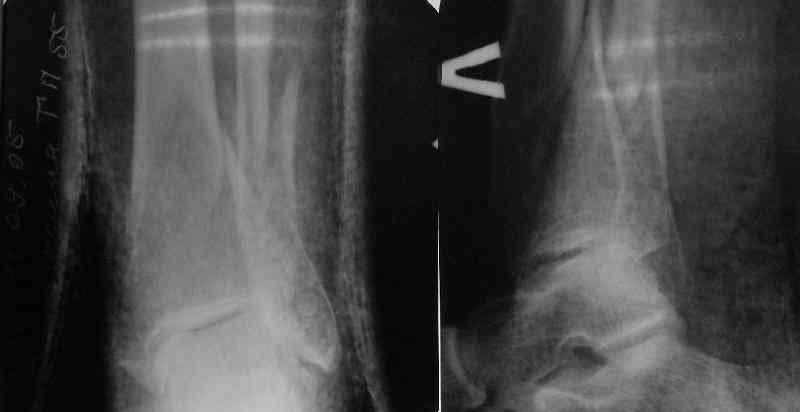

A typical case is attached, also an image with intra-op reduction obtained by a small wire distractor, in the moment of insertion a Poller wire in AP direction. Fixation by a SIGN nail. Despite the fibula was not fixed healing was obtained with the unchanged alignment.

Very interesting application, but is the final position in a little distal varus with some fibula

distraction? Would that have been eliminated by fibula plating?

TDVC> Very interesting application, but is the final position in a

TDVC> little distal varus with some fibula distraction?

At least both the ankle mortise and tibial alignment look acceptable, don't they?

TDVC> Would that have been eliminated by fibula plating?

I am just trying to illustrate that prevention of 1)tibial valgus and 2)loss of reduction can be provided without fibular plating. Small changes of conventional nailing techniques allow to maintain reduction of the tibia reliably without adjunctive fibular stabilization.